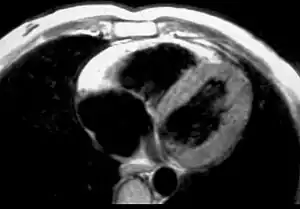

MRI

Fatty infiltration of the RV free wall can be visible on cardiac MRI. Fat has increased intensity in T1-weighted images. However, it may be difficult to differentiate intramyocardial fat and the epicardial fat that is commonly seen adjacent to the normal heart. Also, the sub-tricuspid region may be difficult to distinguish from the atrioventricular sulcus, which is rich in fat.

Cardiac MRI can visualize the extreme thinning and akinesis of the RV free wall. However, the normal RV free wall may be about 3 mm thick, making the test less sensitive.